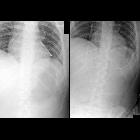

Infant after

feeding tube placementAXR obtained immediately after feeding tube placement (left) shows a feeding tube going down the left mainstem bronchus and then turning up into the lung and increased lucency in the left costophrenic angle presumably due to the feeding tube entering the left pleural space. AXR obtained a minute later after feeding tube repositioning (right) shows the tip of the feeding tube in the antrum of the stomach and a large left pleural air collection with mediastinal shift to the right.The diagnosis was feeding tube malfunction due to placement of the feeding tube through the airway into the lung and pleural space causing a tension pneumothorax.